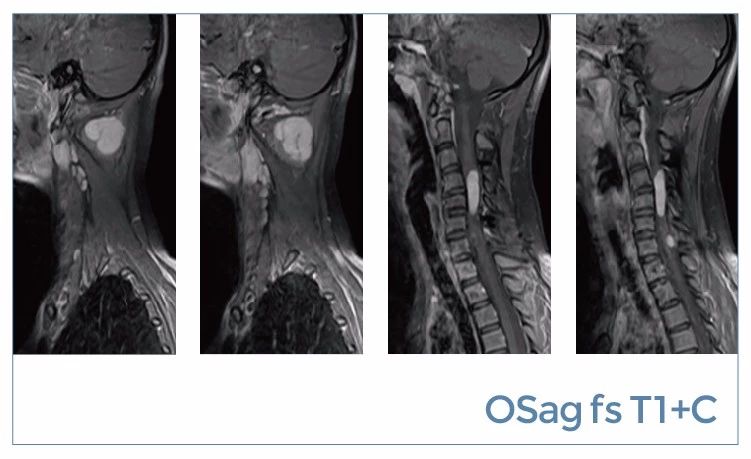

【朗润影像档案】磁共振影像病例分享(编号20190816)